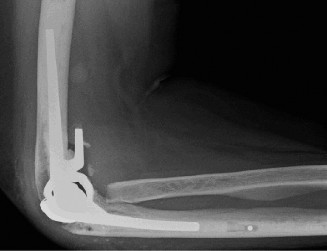

The choice of surgical technique depends on the extent of RA pathology and the specific goals. For advanced RA with significant joint destruction, Total Elbow Arthroplasty (TEA) is the gold standard.

- Linked vs. Unlinked Prostheses:

- Linked (constrained) prostheses: The humeral and ulnar components are mechanically connected, providing inherent stability. These are generally favored for RA due to significant ligamentous laxity, bone loss, and the need for immediate stability. They allow for controlled flexion/extension but limit varus/valgus motion.

- Apply bone cement (polymethylmethacrylate) to both the humeral and ulnar canals, carefully inserting the components. Ensure proper seating and alignment.

- Once both components are cemented and the cement has polymerized, assemble the hinge mechanism (for linked prostheses). This involves connecting the humeral and ulnar components with a linking pin.

- Total Elbow Arthroplasty (TEA) for RA typically involves a linked (constrained) or semi-constrained prosthesis. Linked prostheses provide inherent stability, which is often crucial in RA due to severe ligamentous laxity and bone loss. Unlinked or resurfacing prostheses are generally contraindicated in advanced RA due to the high risk of instability from compromised soft tissues.

- Apply bone cement (polymethylmethacrylate) to both the humeral and ulnar intramedullary canals using a cement gun for optimal pressurization.

- Carefully insert the humeral and ulnar components, ensuring proper orientation and seating. Remove any excess cement. Allow the cement to fully polymerize.

- For linked prostheses, once the components are stable, assemble the hinge mechanism by connecting the humeral and ulnar implants with a linking pin. This step is performed after both components are securely cemented.

- Reduce the joint and assess the stability, range of motion, and tracking throughout flexion and extension, as well as forearm rotation. Adjust soft tissue tension as needed.

- Implant Survival: Modern linked (constrained or semi-constrained) prostheses demonstrate favorable long-term survival rates. Studies report 10-year survival rates ranging from 80-95%, and 15-year survival rates often in the 70-85% range. Aseptic loosening remains the leading cause of revision, emphasizing the importance of meticulous surgical technique, bone cementation, and adherence to post-operative weight restrictions.

- Comparison of Linked vs. Unlinked Designs: For RA patients with significant bone loss and ligamentous insufficiency, linked prostheses (e.g., Coonrad-Morrey, GSB, Discovery) are overwhelmingly preferred due to their inherent stability and superior long-term outcomes compared to unlinked designs, which have higher rates of instability and dislocation.